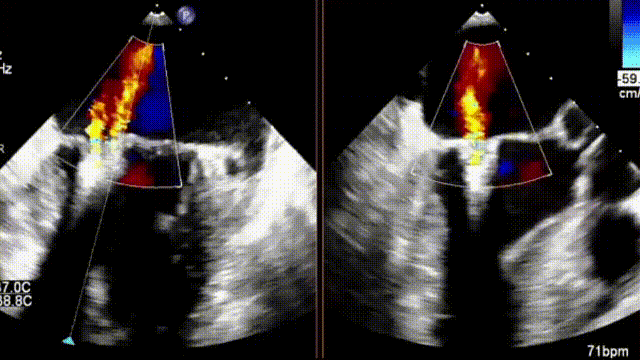

患者男性,86岁,1个月前开始出现夜间阵发性呼吸困难入院。至医院查心电图提示心房颤动,查超声心电图提示二尖瓣前叶(A2偏3区)脱垂并腱索断裂、二尖瓣前叶对合点后移并返流(重度、4级、DMR、Carpentier Ⅱ型)。

术前彩超结果

术后彩超提示返流几乎消失